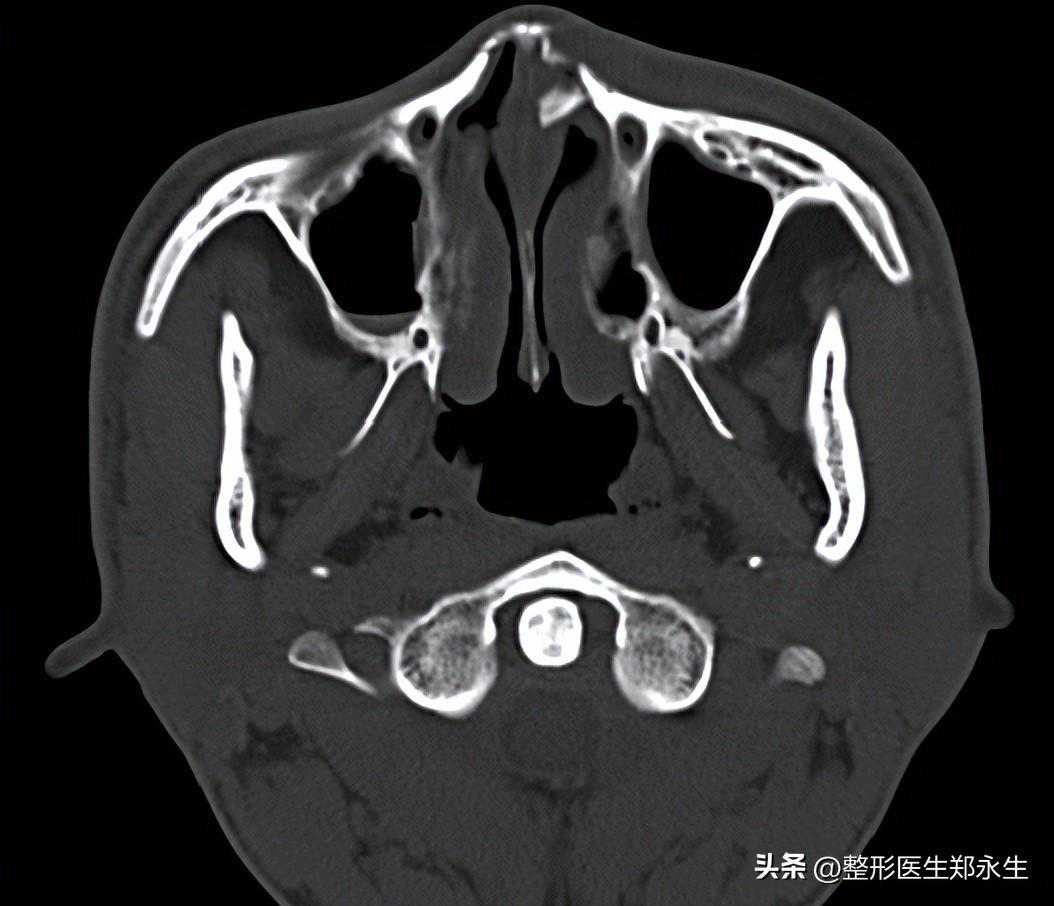

C型:鼻根和鼻尖都处于轴线上,鼻梁中部弯曲呈C型离开中轴线。

S型:很多人把S型称为复杂型歪鼻,它是由于鼻软骨部及骨锥部向不同方向偏曲呈S型。

这种S型歪扭型歪鼻,是由鼻骨、软骨同时歪斜引起的,需要结合上面两步同时矫正鼻骨和鼻中隔软骨,情况较为复杂,很多医院这种混合复杂歪鼻都需要2台手术才能完成。